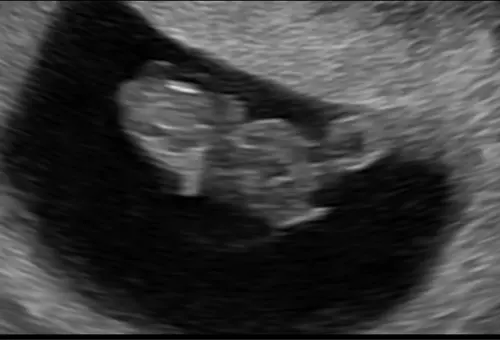

Vandaag een herhaal vitaliteitsecho gehad. Omdat ik 2 weken terug al 7+2 weken dacht te zijn bij de eerste vitaliteitsecho, maar werd teruggezet naar 6+2 weken. Voor mijn eigen gemoedsrust kreeg ik vandaag nog een herhaling. Nu bleek ik toch bijna 9 weken te zijn. Super blij en opgelucht. 🫶🏼🩵🩷